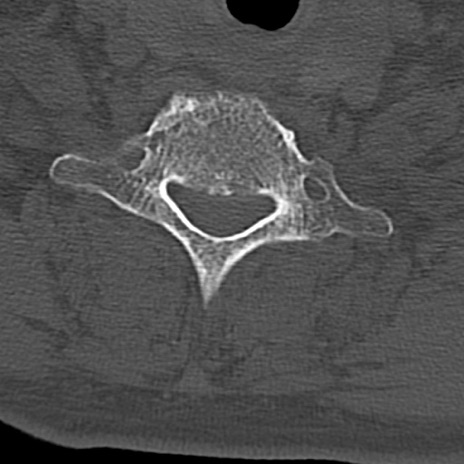

頚椎CT

横断像